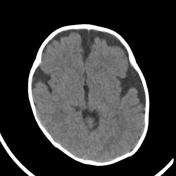

Pediatra atende paciente de 7 meses de vida com aumento do perímetro cefálico, história de gestação e parto sem intercorrência. O perímetro cefálico do nascimento foi de 34 cm e, ao exame físico, apresenta 47 cm, com restante do exame neurológico normal. Foi solicitada uma tomografia computadorizada de crânio (imagem abaixo).

Qual é o diagnóstico?